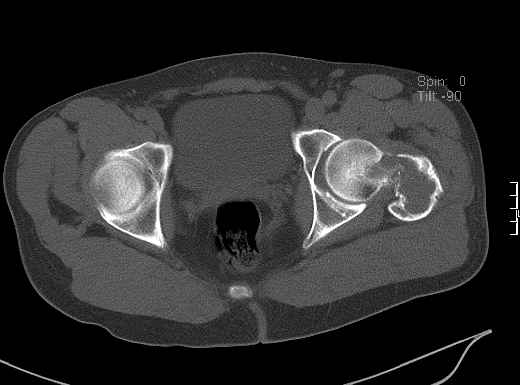

Уважаемые коллеги! Больной (1974 г.р.) травма 26.01.2009г., у пал на ра-боте с высоты своего роста, доставлен в одну из горбольниц Екатеринбурга в травматологическое отделение. На рентгенограмме выявлен патологический перелом чрезвертельной области левого бедра.

Доброкачественная опухоль (ОБК?, энхондрома?), по данным RS. Дополнительно произведено КТ. Наложено скелетное вытяжение.

Прилагаются: рентгенограмма и данные СТ

По данным рентгенограммы и СТ диагноз определить в данном случае нельзя. При дифдиагнозе можно предполагать костную кисту, остеокластому, хондрому; в нашей клинике был подобный случай - гистологически верифицирована хондромиксоидная фиброма.